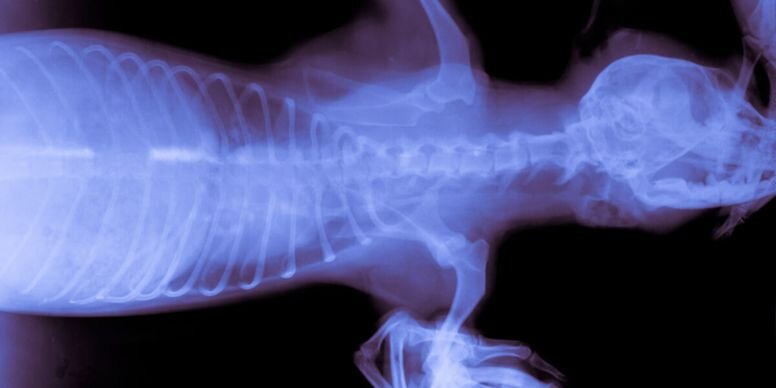

Сначала Бо направили на рентген. По результатам исследования доктор только покашлял. Заслышав необыкновенный кашель от специалиста, тут же Люси схватилась за сердце.